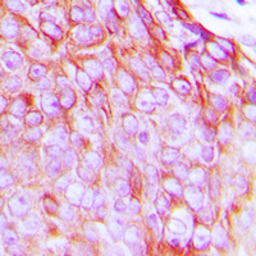

IHC-P analysis of formalin fixed human breast cancer tissue section using GTX55015 Insulin Receptor (phospho Tyr1322) antibody.

Antigen retrieval : Heat mediated antigen retrieval with sodium citrate buffer (pH 6.0)